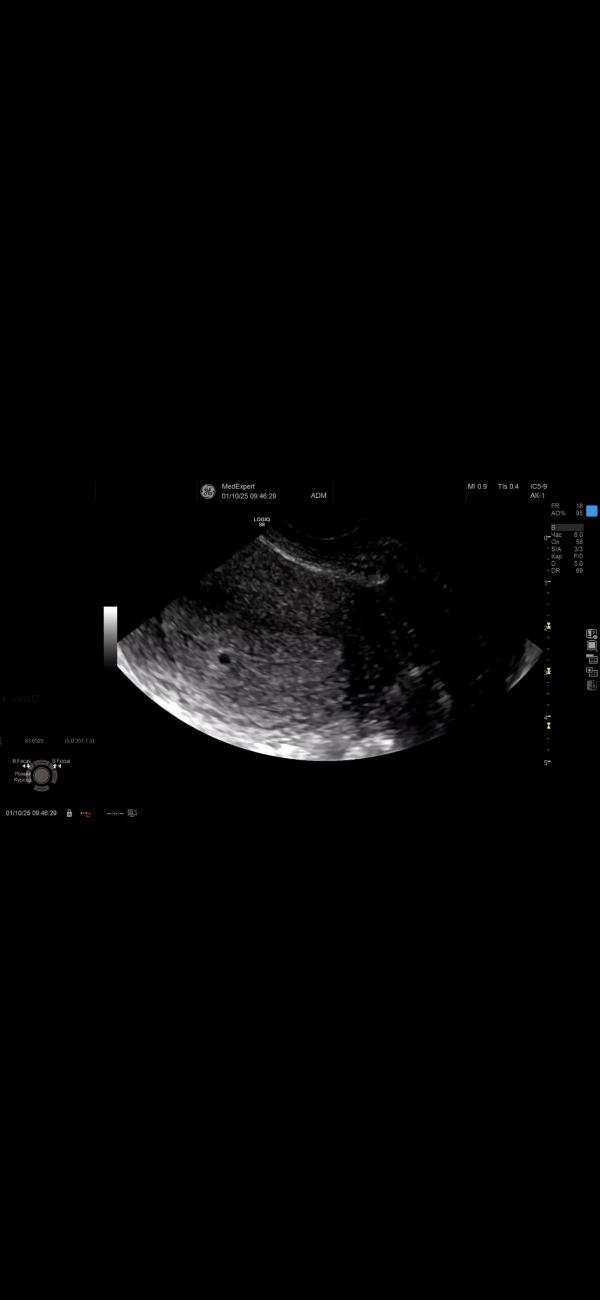

сходила на узи, сегодня 5нед1д

пя 4.3мм

следующее узи через две недели только